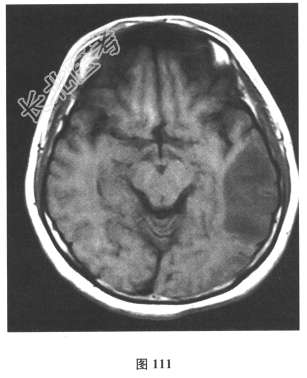

- 简答题2、脑脊液检查:常规、生化均正常,CSF-病毒TORCH(-),抗Hu、Yo、Ri均阴性,OB、MBP正常。血清抗Hu、Yo、Ri均阴性。颅脑MRI显示左颞枕、右顶枕多发长T₁、长T₂信号,Flair高信号,病变累及皮质及皮质下白质,病灶无强化,见图108~图114。根据颅脑MRI,需要鉴别的疾病应是